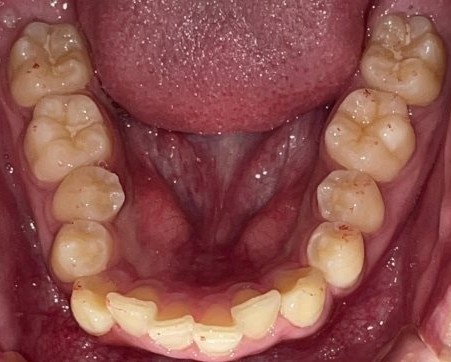

Before

After

矯正の種類 / invisalign GO

年齢・性別 / 30代女性

主訴  /  叢生、交叉咬合

治療期間 / 17ヶ月

費用 / 簡易検査 5,000円(税別) 精密検査 30,000円(税別)

両顎マウスピース 450,000円(税別) 両顎リテイナー料 60,000円(税別)

※マウスピース交換時別途調節料5,000円(税別)

副作用 / 口内炎・歯の移動に伴う痛み・知覚過敏 ※数日で収まる場合が多いです

リスク / 後戻り防止の為、夜のみマウスピースで保定を指示